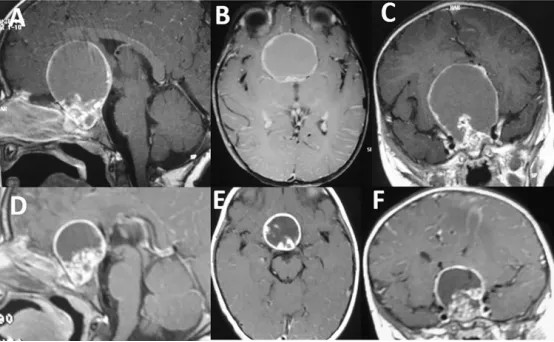

一名11歲男童的巨大顱咽管瘤。

請(qǐng)注意在釓增強(qiáng)T1序列上可見(jiàn)大型強(qiáng)化囊性成分(圖A、B、C),其范圍延伸至前、中、后顱窩。同時(shí)存在明顯的雙側(cè)腦室積水(圖A–E)。在FLAIR序列上,囊液信號(hào)較腦脊液為高(圖D)。需要注意的是,腫瘤的實(shí)質(zhì)成分僅占一小部分(圖E,箭頭所示),但其累及Willis環(huán)區(qū)域(圖F,星號(hào)所示)。